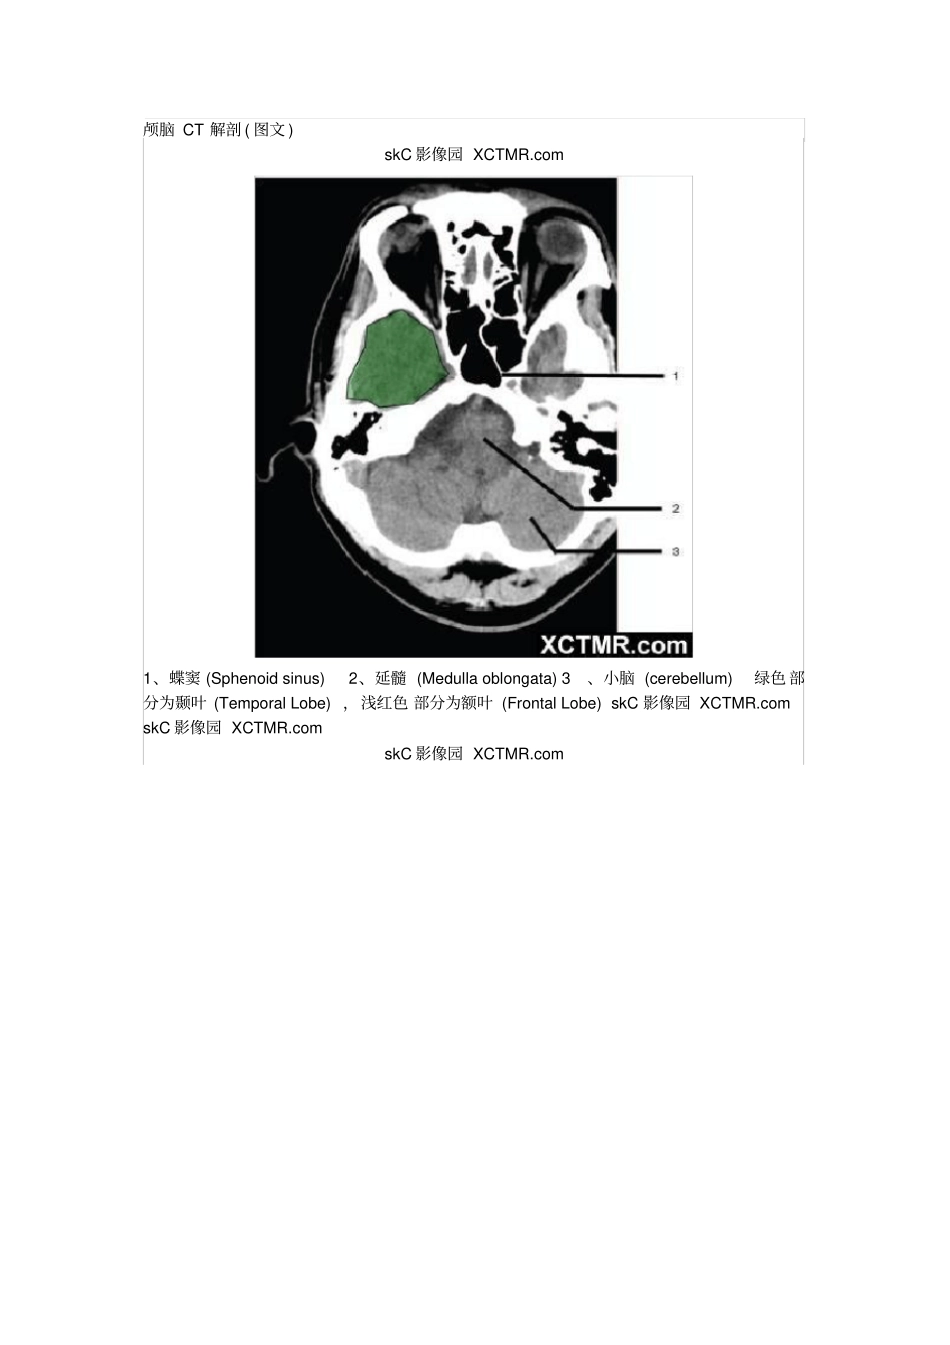

颅脑CT解剖(图文)skC影像园XCTMR.com1、蝶窦(Sphenoidsinus)2、延髓(Medullaoblongata)3、小脑(cerebellum)绿色部分为颞叶(TemporalLobe),浅红色部分为额叶(FrontalLobe)skC影像园XCTMR.comskC影像园XCTMR.comskC影像园XCTMR.com4、第四脑室(Fourthventricle)5、小脑中角(Middlecerebellarpeduncle)6、乙状窦(Sigmoidsinus)7、颞骨及乳突气房(Petroustemporalboneandmastoidaircells)8、桥小脑角(Cerebellopontineangle)9、脑桥(Pons)10、垂体窝(Pituitaryfossa)绿色部分为颞叶(TemporalLobe),浅红色部分为额叶(FrontalLobe)skC影像园XCTMR.comskC影像园XCTMR.com11、小脑蚓部(Cerebellarvermis)12、基底动脉(Basilarartery)13、桥前池(Prepontinecistern)14、鞍背(Dorsumsellae)15、侧脑室颞角(Temporalhornoflateralventricle)绿色部分为颞叶(TemporalLobe),浅红色部分为额叶(FrontalLobe)skC影像园XCTMR.comskC影像园XCTMR.com16、环池(Ambientcistern)17、角间池(Interpeduncularcistern)18、大脑角(Cerebralpeduncle)19、侧裂池(Sylvianfissure)绿色部分为颞叶(TemporalLobe),浅红色部分为额叶(FrontalLobe)skC影像园XCTMR.comskC影像园XCTMR.com20、小脑上池(Thirdventricle)21、侧脑室前角(Frontalhornoflateralventricle)21a、第三脑室(Thirdventricle)绿色部分为颞叶(TemporalLobe),浅红色部分为额叶(FrontalLobe),黄色部分为枕叶(OccipitalLobe)skC影像园XCTMR.comskC影像园XCTMR.com22、尾状核头部(Headofcaudatenucleus)23、岛叶(Insularcortex)24、外囊(Externalcapsule)25、豆状核(Lentiformnucleus)26、丘脑(Thalamus)绿色部分为颞叶(TemporalLobe),浅红色部分为额叶(FrontalLobe),黄色部分为枕叶(OccipitalLobe)skC影像园XCTMR.comskC影像园XCTMR.com27、纵裂(Interhemisphericfissure)28、内囊前肢(Anteriorlimbofinternalcapsule)29、内囊膝部(Genuofinternalcapsule)30、内囊后肢(Posteriorlimbofinternalcapsule)31、侧脑室三角区及脉络丛钙化(Trigoneoflateralventricleandcalcifiedchoroidplexus)32、侧脑室枕角(Occipitalhornoflateralventricle)绿色部分为颞叶(TemporalLobe),浅红色部分为额叶(FrontalLobe),黄色部分为枕叶(OccipitalLobe),褐色部分为顶叶(ParietalLobe)skC影像园XCTMR.comskC影像园XCTMR.com33、侧脑室体部(Bodyoflateralventricle)34、放射冠(Coronaradiata)浅红色部分为额叶(FrontalLobe),黄色部分为枕叶(OccipitalLobe),褐色部分为顶叶(ParietalLobe)skC影像园XCTMR.comskC影像园XCTMR.com35、半卵圆中心(Centrumsemiovale)浅红色部分为额叶(FrontalLobe),黄色部分为枕叶(OccipitalLobe),褐色部分为顶叶(ParietalLobe)额骨(FB—Frontalbone)顶骨(PB—Parietalbone)枕骨(OB—Occipitalbone)skC影像园XCTMR.comskC影像园XCTMR.com36、中央前回(Pre-centralgyrus)37、中央沟(Centralsulcus)38、中央后回(Post-centralgyrus)浅红色部分为额叶(FrontalLobe),褐色部分为顶叶(ParietalLobe)skC影像园XCTMR.comskC影像园XCTMR.com浅红色部分为额叶(FrontalLobe),褐色部分为顶叶(ParietalLobe)skC影像园XCTMR.comskC影像园XCTMR.com浅红色部分为额叶(FrontalLobe),褐色部分为顶叶(ParietalLobe)skC影像园XCTMR.com